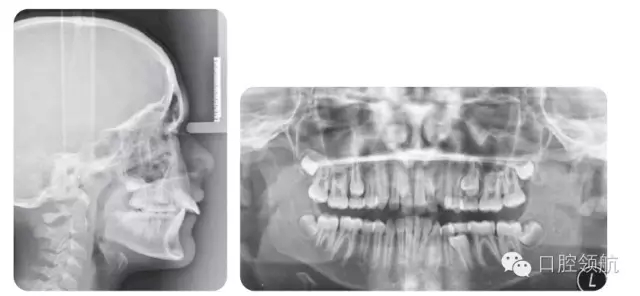

11歲的患者,因其過于前突的上頜前牙而就診。

試討論口外檢查與影像學檢查在該病例治療方案確定中的相互關(guān)系(圖2.48與圖2.49)

可以通過口外檢查了解該患者在咬合情況以外的頜面骨骼及軟組織的情況。

對于該病例來說,錯牙合畸形是由多因素引起的:

● 前后矢狀向以及垂直向的頜骨不調(diào)。

● 骨性Ⅱ類短面型(下面高短,下頜平面角?。?。軟組織檢查發(fā)現(xiàn)該患者上唇長度較短,在一定程度上增加了其切牙及牙齦的暴露量。下唇存在因長期抵在上切牙腭側(cè)而形成的印痕,這也使覆蓋進一步加大。